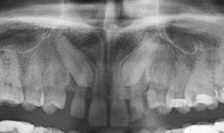

Раздаточный материал:

Автор вопроса в шутку назвал обладателя этой рентгенограммы антиИКСОМ. Назовите ИКСА.